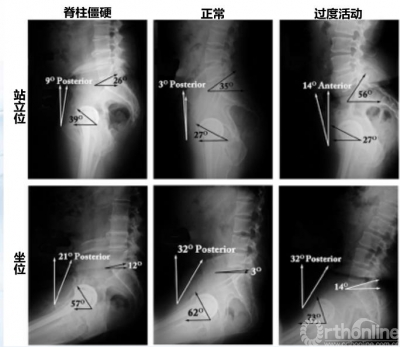

骨盆活动度与体位变化对THA的影响

上述介绍了从仰卧位到站立位的骨盆矢状面变化,那么不同体位对THA术后人工关节有何影响?既往系统综述显示,从769项报道中筛选12个RCT研究中,过高的骨盆活动度(站立位和坐位)骨盆前倾角变化较大,增加了假体撞击和脱位的风险。

图4 站立位到坐位髋臼角度的变化

图5 1例髋关节脱位患者髋臼角度的变化

坐位时髋臼前倾角变大,可以影响稳定性、增加边缘磨损、甚至脱位。对于骨盆活动度大患者,髋臼外展角>50°, 前倾角>25°,脱位的危险也明显增大。既往研究显示,从站立位到坐位,髋臼前倾增加7.1°,骨盆后倾增加14.5°;在矢状面上,坐位时骨盆后倾增加30°,髋臼前倾增加30.2°。